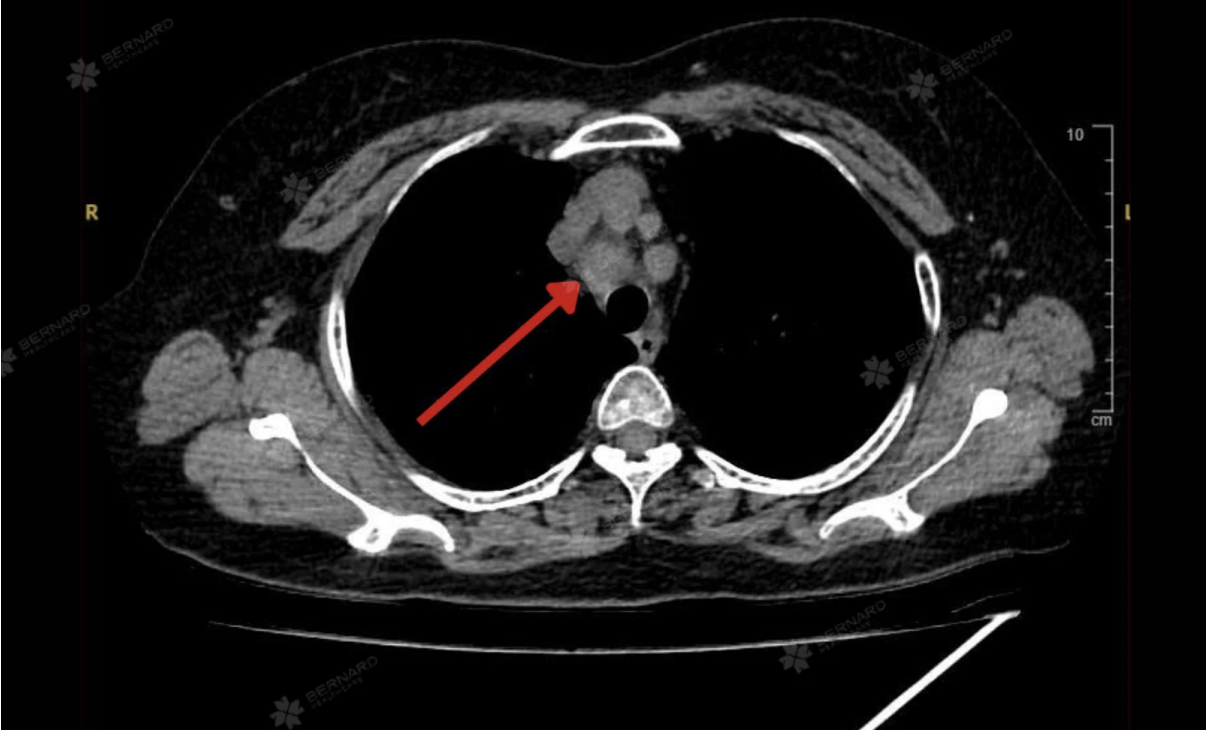

Kết quả CT Scan của bà K. cho thấy tổn thương choán chỗ thùy dưới phổi trái (S10), kích thước khoảng 1,5 x 2,5 cm, đậm độ mô, bờ tua gai và có co kéo mô phổi xung quanh. Những đặc điểm này gợi ý u phổi ác tính, cần kết hợp sinh thiết để xác định chính xác bản chất tổn thương.

Đáng chú ý, CT Scan còn ghi nhận một số hạch trung thất nghi di căn, với hạch lớn nhất thuộc nhóm 2, cùng các nốt nhỏ quanh rãnh liên thùy bé phổi phải (đường kính khoảng 3 mm) và nốt dưới màng phổi thùy lưỡi (đường kính khoảng 7 mm).

Đây có thể là dấu hiệu cho thấy tổn thương đã bước vào giai đoạn di căn hạch trung thất, tuy nhiên chưa ghi nhận bằng chứng lan rộng đến các cơ quan xa.